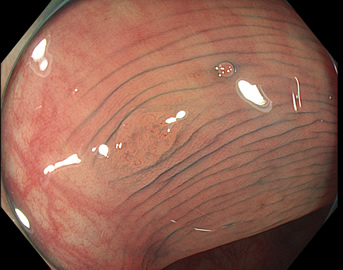

TXIは、「画像の構造を強調する」技術です。これは特別に目新しいものではありません。パソコンの画像編集ソフトや、スマホのアプリでも御馴染みの技術です。しかし、「どのような構造強調が実際に、内視鏡に一番、合うか?(強すぎると不自然になる!)」は、難しい(アナログ的な)課題です。オリンパス社は数タイプのTXIモードを用意しました。半年間の試行錯誤の末、今では下記のモードがベストと判断しました。そして今では「TXI無しの内視鏡は不要(フルタイムTXI)」というまで常用しています。

以下に実例を挙げます

写真だけ、見ると「言われてみるとTXIの方が認識しやすい。でも僅かの差」と感じるでしょうが、この「僅かの差」が、人間の脳での検出には大きな差になります。青い色素(インジゴ・カルミン)が非常に強調され、粘膜の凸凹が明瞭になるのが特徴です。

通常観察 TXIモード